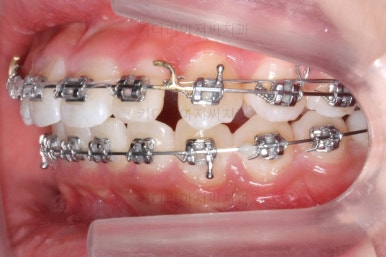

처음 장치를 부착한 이 후 8개월이 흐른 시점이네요. 꽤나 오랫동안 천천히 송곳니를 가지런하게 해줘요.

치료 10개월째의 모습입니다.

이정도면 다 끝난 것 같은 느낌이 드시지 않나요? 과개교합도 개선시켰고 매복치아 덧니도 가지런하게 했어요.

근데 문제는 지금부터였어요.

작은 앞니가 왜소치이다 보니 윗니에는 틈이 남아있고 교합도 조금 엉성한 모습이에요.